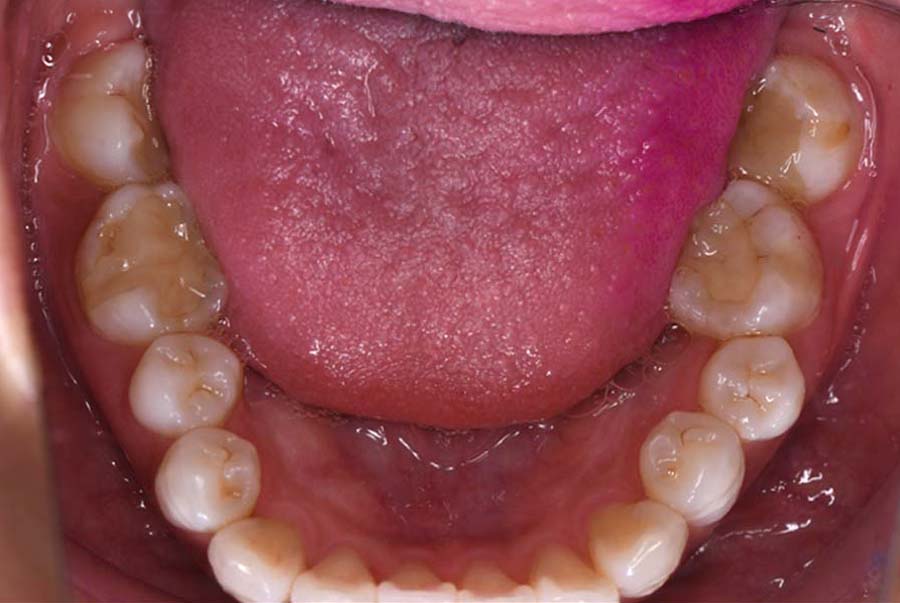

スプリント使用後、

補綴治療をした症例

治療内容 ①スプリントを装着

②副子を装着

③2024年4月 口腔内反映開始

④副子を入れた状態の所まで咬合を挙上

(バイトアップ)

⑤2024年5月 上顎前歯部8本へ仮歯(TEK)

を装着